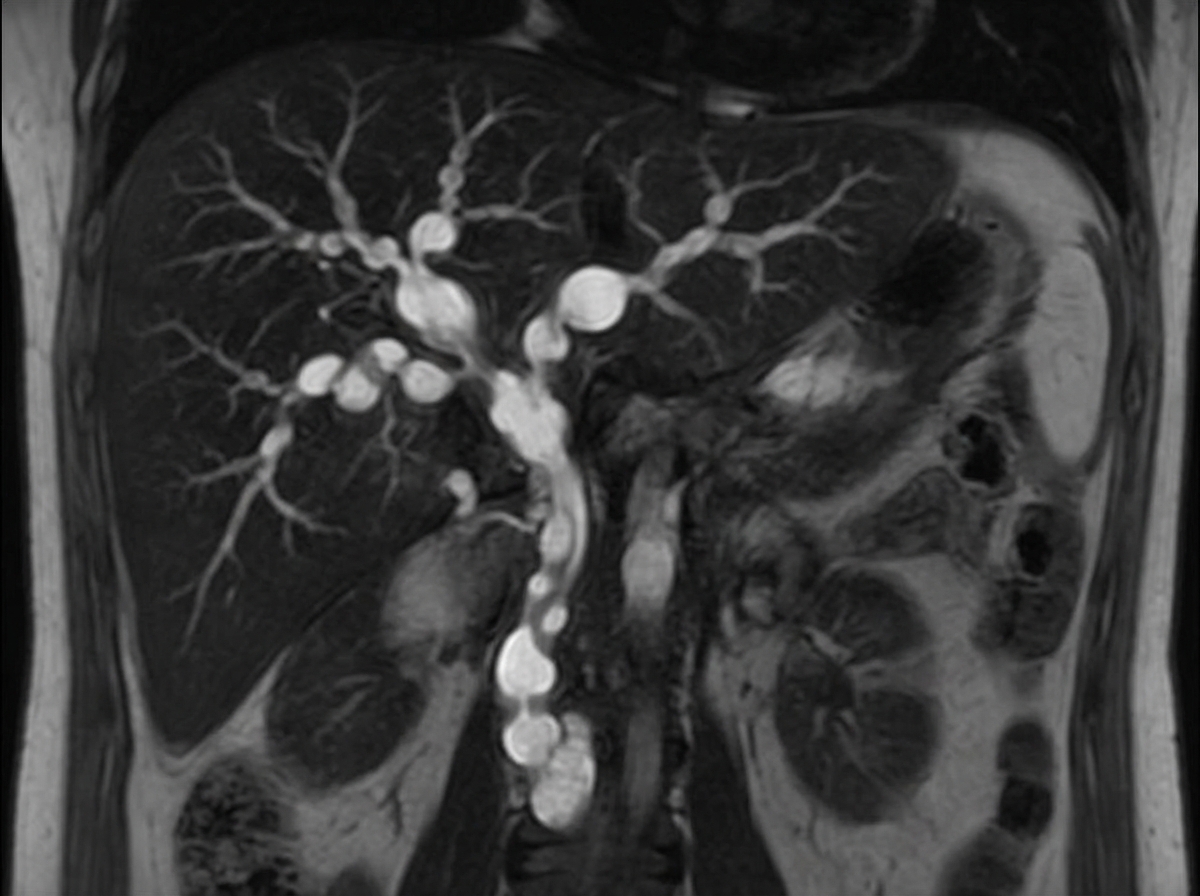

A 45-year-old male presented with recurrent attacks of cholangitis. MRCP and ERCP findings are suggestive of this condition. What is the treatment of choice for this condition?

Explanation: ***Liver transplantation*** - Primary sclerosing cholangitis (PSC) is a **progressive disease** with no effective medical therapy, making **liver transplantation** the only definitive treatment for advanced disease. - Given the **recurrent cholangitis** and characteristic **MRCP/ERCP findings** (beaded appearance), this patient likely has end-stage PSC requiring transplantation. *ERCP with stenting* - ERCP with stenting is a **palliative procedure** used for **dominant strictures** in PSC to improve bile drainage temporarily. - It does **not halt disease progression** and is not considered the definitive treatment for PSC. *High dose ursodeoxycholic acid* - **Ursodeoxycholic acid (UDCA)** has shown **no proven benefit** in PSC and may actually worsen outcomes in high doses. - Current guidelines **do not recommend UDCA** for PSC treatment due to lack of efficacy in preventing disease progression. *High dose prednisolone* - **Corticosteroids** like prednisolone are **not effective** in PSC and do not improve long-term outcomes. - PSC is **not an autoimmune condition** that responds to immunosuppression like autoimmune hepatitis does.